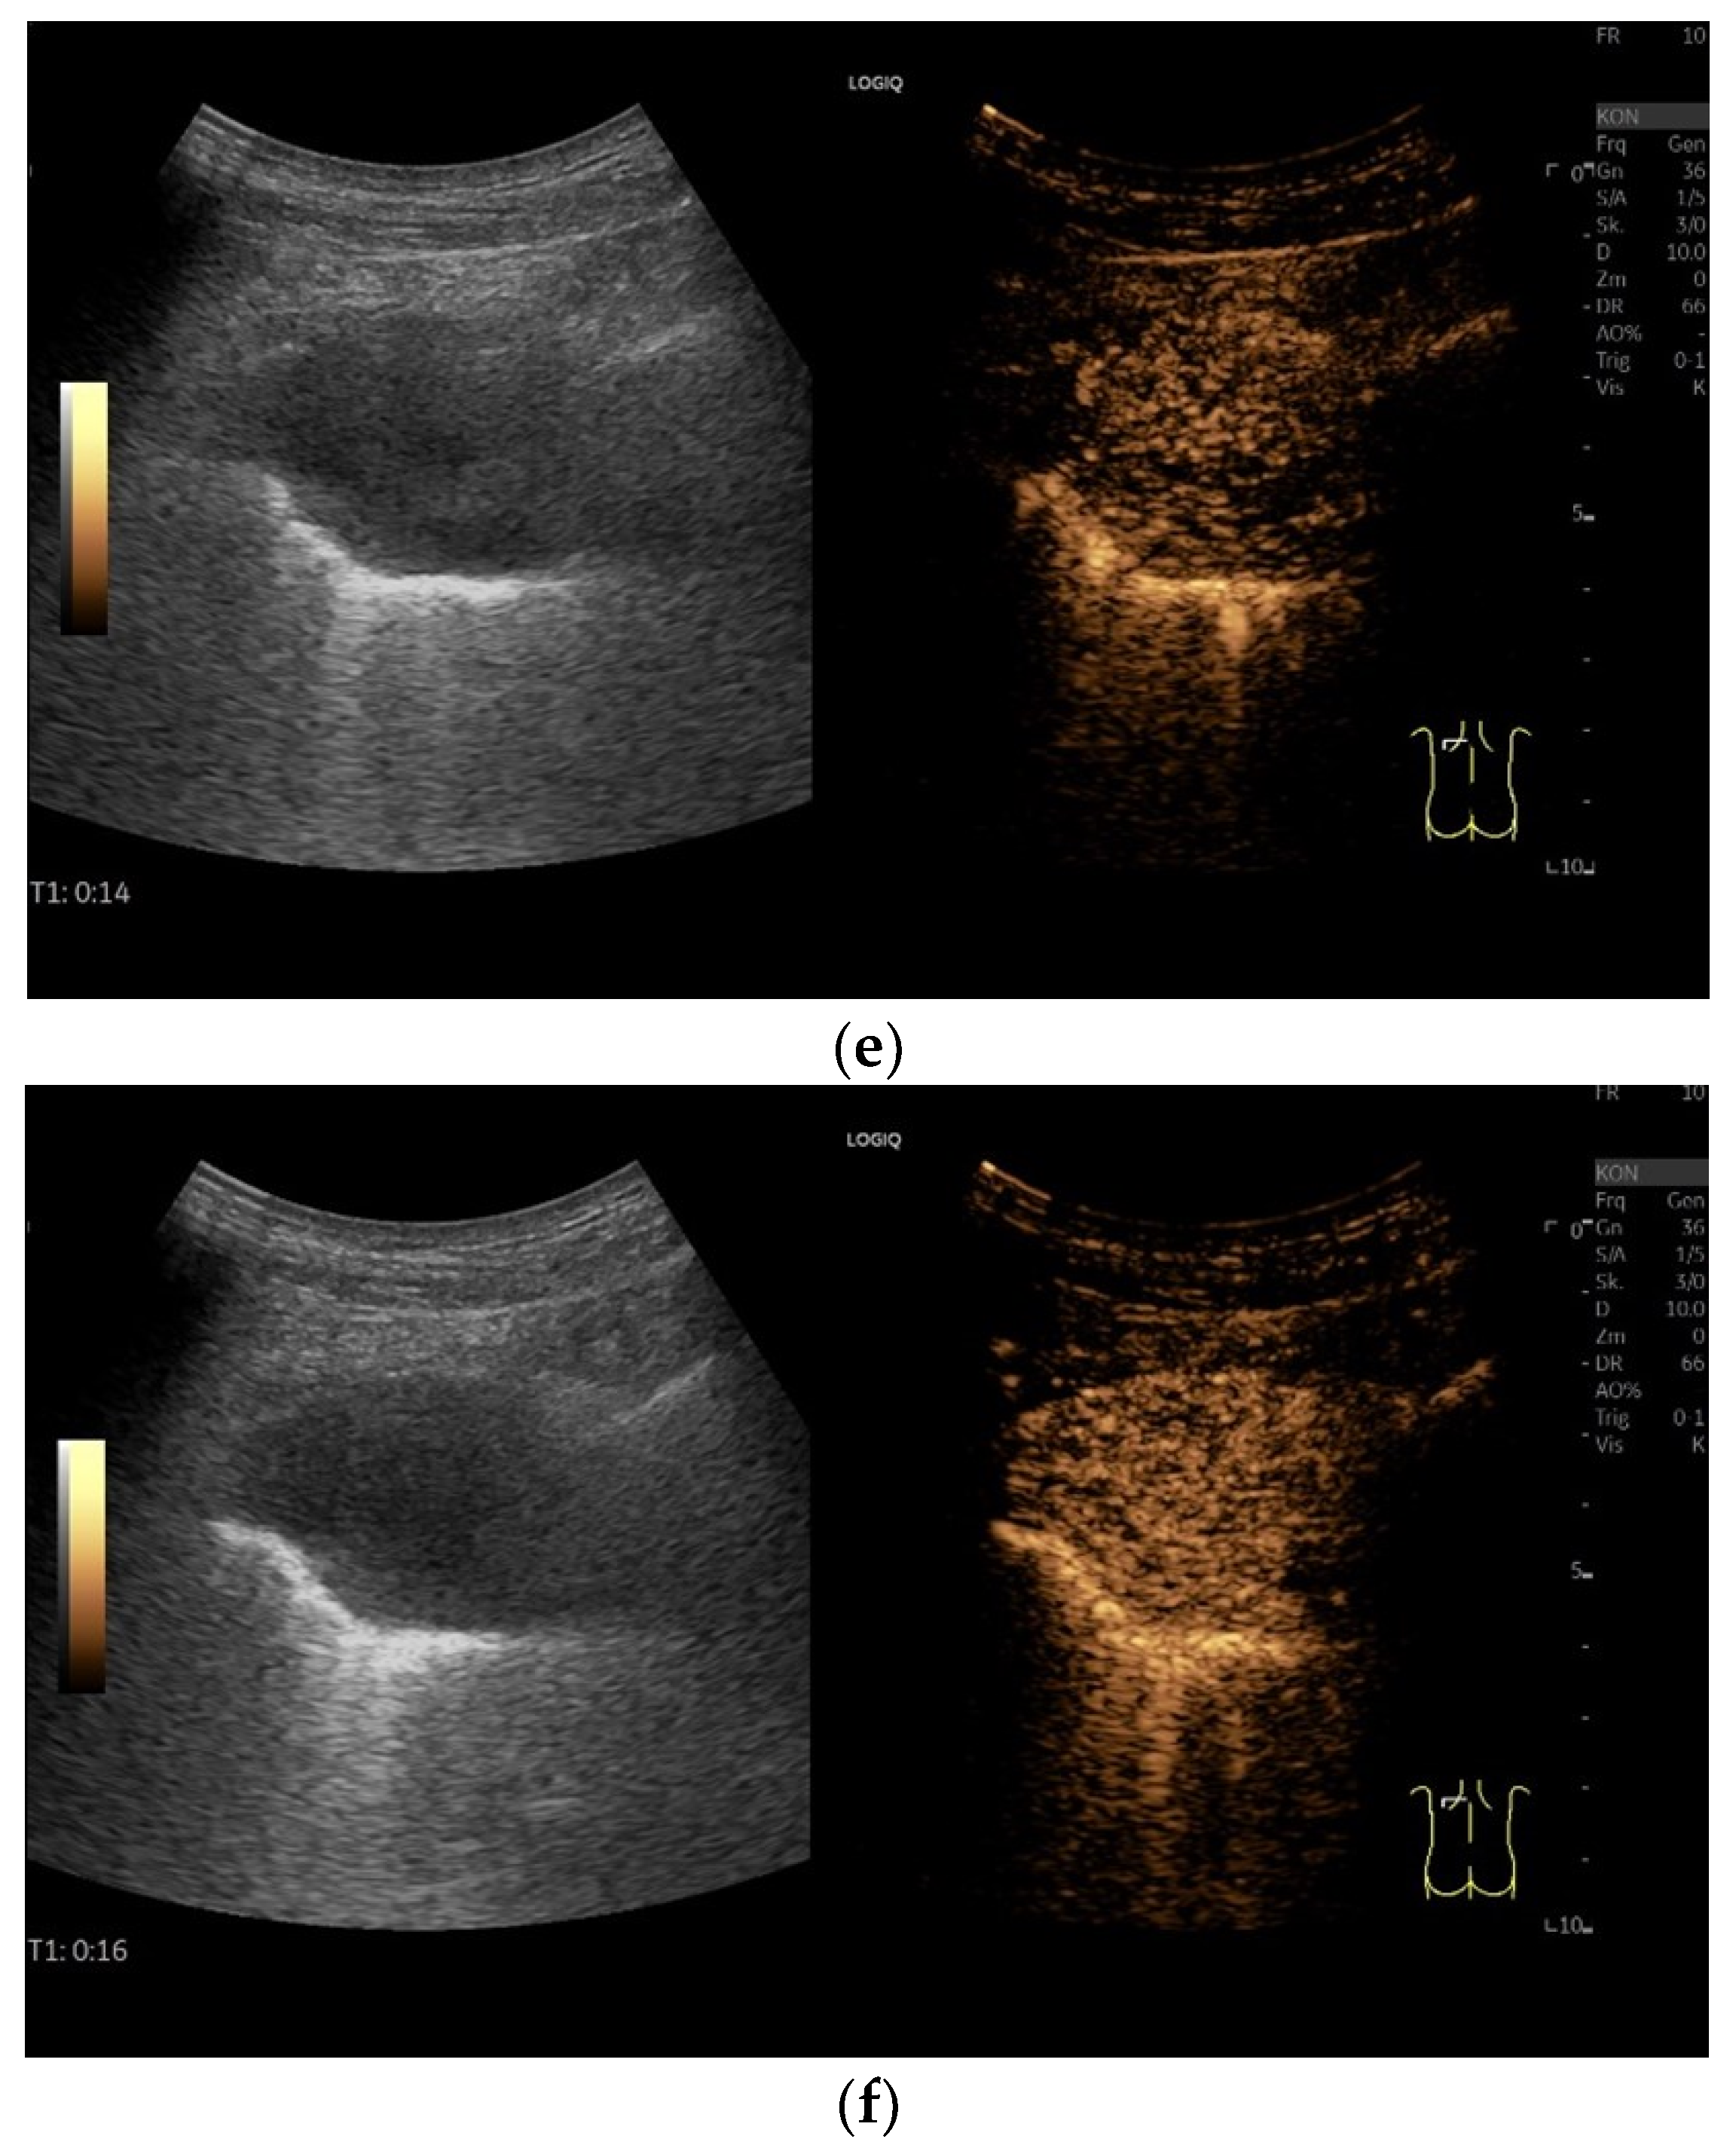

| Benign solitary fibrous tumor | Smoothly bordered, hypoechoic. Examples with a nodular shape have been described. Larger tumors can have cystic parts. With few data and based on our example, the solid parts are hyper-enhanced in CEUS. |